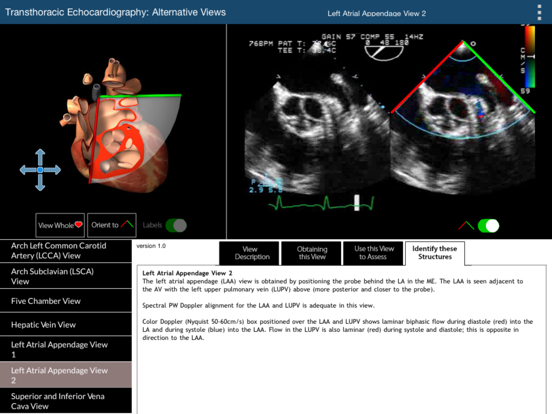

The primary challenge in learning TEE is translating the two dimensional echocardiographic image into a visualization of the complex three-dimensional (3D) structure of the heart. This TEE Alternative Views app provides a learning environment where users can explore 19 non-standard but complimentary 2D TEE views using two visualization methods simultaneously: (1) a rotatable 3D heart model with an echocardiographic plane and (2) the associated TEE clip. The 3D heart model and echo plane can be rotated, helping to relate the echocardiographic image to heart structures. Part of the heart above the echo plane can be removed, revealing the internal cardiac structures that correspond to the TEE image. This app will enable the user to perform a more complete TEE study than can be obtained from the 20 standard TEE views. For the 20 standard TEE views, please refer to our TEE Standard Views app. The 19 alternative TEE views illustrated in this app are: Coronary Sinus View (100 Degrees) Coronary Sinus View (0 Degrees) Tricuspid Valve Transgastric Short Axis View Tricuspid Valve Mid-Esophageal View Pulmonic Valve Transgastric View Pulmonary Artery Mid Esophageal Right Coronary Artery View Coronary Arteries View Left Pulmonary Veins View Right Pulmonary Veins View Right Upper Pulmonary Vein View Arch Innominate Artery View Arch Left Common Carotid Artery (LCCA) View Arch Subclavian (LSCA) View Five Chamber View Hepatic Vein View Left Atrial Appendage View 1 Left Atrial Appendage View 2 Superior and Inferior Vena Cava View